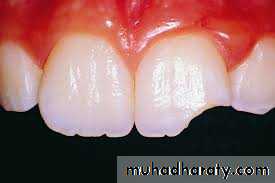

Direct exposure of the dental pulp to the oral cavity is the most obvious route of endodontic infection. Caries is the most common cause of pulp exposure, but bacteria may also reach the pulp via direct pulp exposure as a result of iatrogenic restorative procedures or trauma